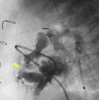

Methods/results: A full-term infant girl (2.9 kg) referred for hypoxia (80% with room air) and murmur was found to have DORV, interrupted inferior vena cava, and restrictive VSD (95-mmHg gradient). Transhepatic access was performed, and an internal mammary (IM) catheter was advanced through the atrial septal defect and into the left ventricle. By transesophageal echocardiographic guidance, a Baylis radiofrequency perforation wire was used to cross the ventricular septum, and the defect was enlarged using a 4-mm cutting balloon. A bare metal stent then was deployed to maintain the newly created VSD. The patient did well after the procedure but required pulmonary artery banding 4 days later. She returned 5 months later with cyanosis and the development of obstructing right ventricle muscle bundles, requiring further surgical palliation.